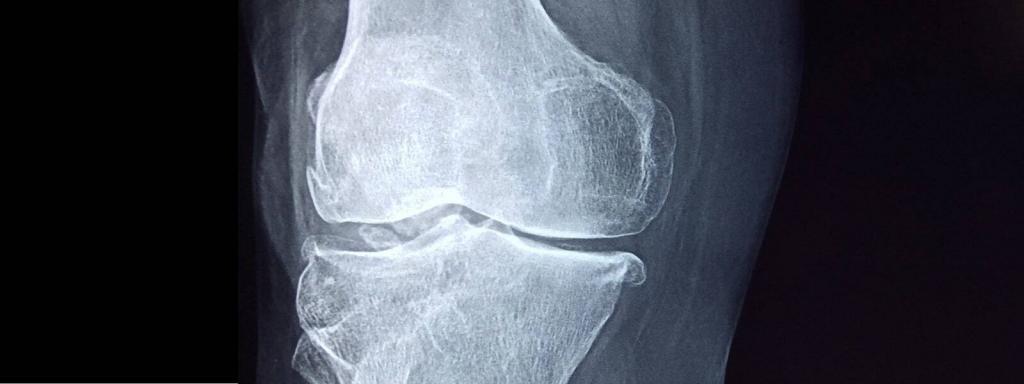

Можно ли производить костную ткань вне человеческого организма? Казахстанские ученые разработали уникальный проект, отвечающий на этот вопрос. Группа ученых Назарбаев Университета под руководством профессора Даны Акилбековой разработала новую технологию, позволяющую воспроизводить человеческие кости и печатать ее 3D-модели. Процесс осуществляется с помощью шведского принтера.